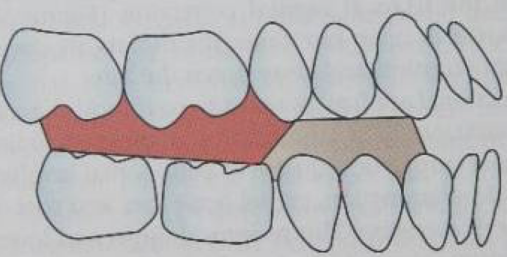

另外,我還看到有患者後牙用樹脂墊高。醫師解釋在矯正上後牙墊高並非只是為了避免咬掉Bracket,而是要考慮完整的治療設計。後牙墊高可以消除咬合干擾,可以用在解除Cross Bite。但是其會對後牙Intrusion,導致Deep Bite加深,並不適用在Low angle的Class II患者。若Low angle的Class II患者會咬到Bracket,可以考慮修型Bracket。